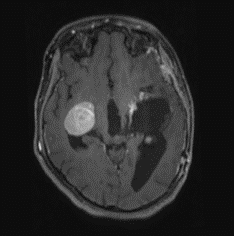

MRI outside hospital was done which was re-reported in our centre as Bilateral temporal lobe enhancing lesions. The left temporal lobe mass was larger in size and causing right-sided midline shift causing compression of the third ventricle with upstream hydrocephalus and transependymal seepage. These masses were reported as of neoplastic etiology, likely low-grade gliomas. Then MRI Brain with contrast was repeated which showed Bilateral intraventricular masses which are more or less stable in sizes causing hydrocephalus and compression effect at the level of the third ventricle towards the right side. Differentials included intraventricular tumors. No adjacent invasion is seen.

Figure 1: Lesion on T2 axial brain MRI.

Figure 2: Lesion on T1 post contrats axial brain MRI.

The mean age of onset with nodal disease is 20.6 years with a male to female ratio of 1.4:1 [6,17]. Patients who develop intracranial involvement, however, become symptomatic at a mean age of 34.9 years, with a strong male preponderance. In intracranial RDD, the most involved structures are the suprasellar region, cerebral convexity, parasagittal region, cavernous sinus, and petroclival region [18,19]. Radiologically, the typical MRI findings include isointense to hypointense T1-weighted signals and hyperintense T2-weighted signals with homogeneous enhancement post-contrast. Bitemporal lesions often exhibit a dural-based, meningioma-like appearance [20]. Intracranial RDD is commonly confused with meningioma and requires tumor histopathology and immunohistochemistry for its definitive diagnosis.